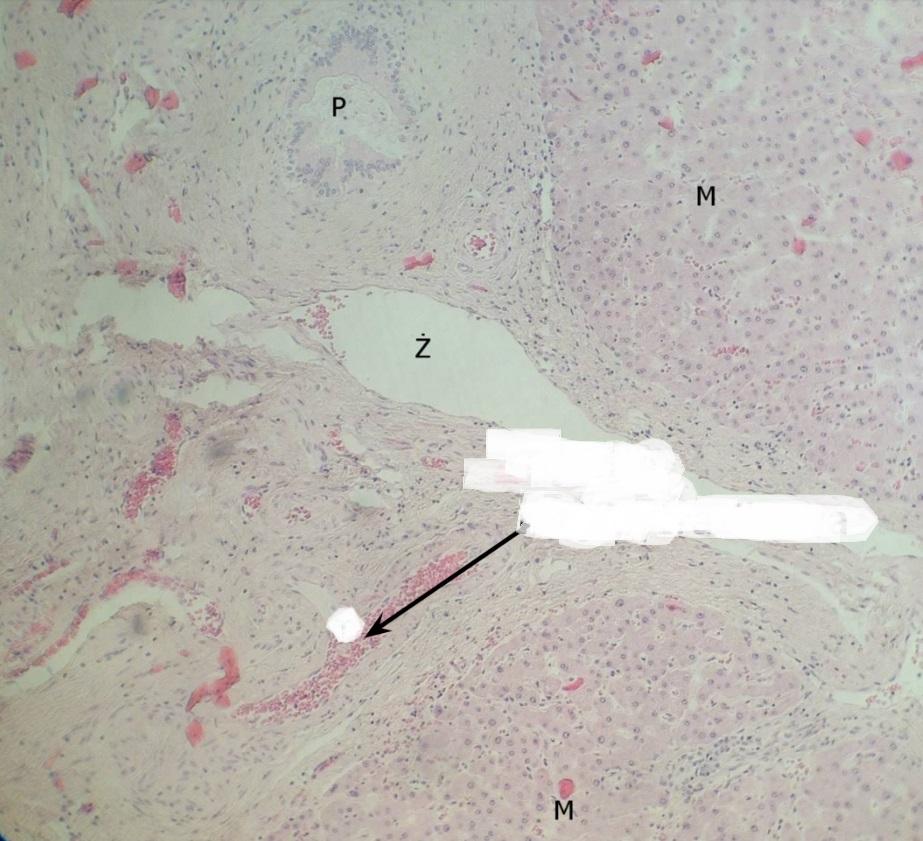

Pytanie 444

żyła międzyzrazikowa - największa z triady (wątroba świni, triada)

Pytanie 445

tętnica międzyzrazikowa - widać wyraźnie mięśniówkę (wątroba świni, triada)

Pytanie 446

kanalik żółciowy międzyzrazikowy - wygląda, jak pętla korali (wątroba świni, triada)

Pytanie 447

sinusoidy - biała przestrzeń (wątroba świni)